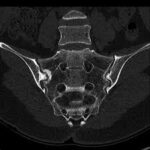

CT Scan Bilateral Sacroiliac Joint

A CT scan bilateral sacroiliac joint is a specialized imaging test that provides detailed images of the sacroiliac (SI) joints, located in the lower back and pelvis. This scan helps doctors identify a variety of conditions affecting the SI joints, including arthritis, fractures, inflammation, and soft tissue injuries. The bilateral sacroiliac joint CT scan is particularly useful for detecting issues that may not be visible through regular X-rays.

What is CT scan Bilateral Sacroiliac Joint?

A CT scan bilateral sacroiliac joint (also known as bilateral sacroiliac joint imaging) is a medical procedure that uses X-ray technology to create cross-sectional images of the sacroiliac joints. By offering high-resolution images, this procedure allows healthcare providers to closely examine the bones, cartilage, and surrounding tissues of the SI joints. The use of contrast dye can help make the images clearer, allowing doctors to find conditions like fractures, arthritis, and swelling more easily. It is often suggested when X-rays or MRIs are not enough to identify specific issues with the sacroiliac joints.